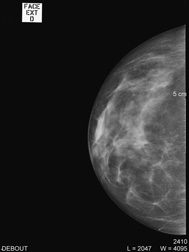

| Debout, le sein légèrement comprimé, deux clichés sont réalisés de face et en oblique sur chaque coté ; d’autres clichés localisés pour mieux analyser une zone peuvent aussi être effectués. |